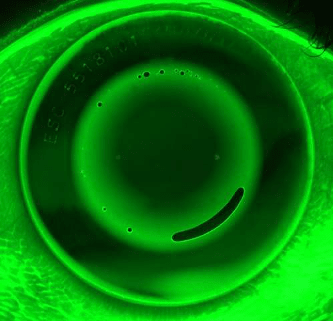

Air Bubbles

Bubbles arise when air becomes trapped between the lens and cornea, typically upon lens application. Small-sized bubbles are common and do not usually cause corneal or visual complications (Figure 4).

Moderate to large-sized bubbles can cause double-ring patterns on topography and vision complaints (Figures 4, 5, and 6). If there is no compromise to corneal health or vision, application bubbles can be monitored without lens adjustments. If corneal health or vision complaints are observed, advise the patient to use a more viscous application drop, apply the lens face down, and immediately go to sleep. If the air bubbles persist, the sagittal height of the lens may be too high and require flattening of the reverse curve to resolve the issue.